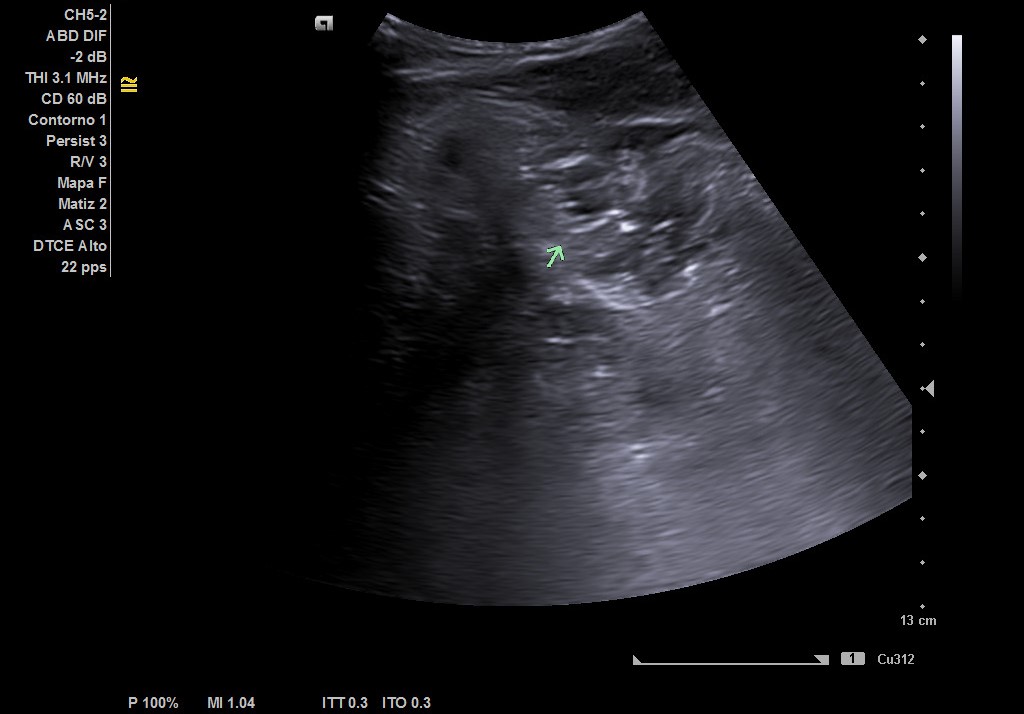

Hígado de tamaño, forma y ecoestructura conservadas, con parénquima homogéneo. Vena porta de calibre conservado.  Ausencia de signos de dilatación de la vía intra o extrahepática. Vesícula biliar de paredes finas, sin contenido ecogénico en su interior. Páncreas de características normales. Riñones de tamaño y localización conservada, sin hidronefrosis. En FID imagen heterogénea delimitada, de 50x30 mm, con posible edema de pared y focos ecogénicos en su interior.

Complicaciones post-quirúrgicas (Plastrón inflamatorio vs absceso). Diagnóstico diferencial: Diverticulitis colon derecho. Tras ecografía realizada por Radiología en el servicio de Urgencias y valoración por Cirugía General se llegó al diagnóstico de plastrón inflamatorio y colección postapendicectomía.